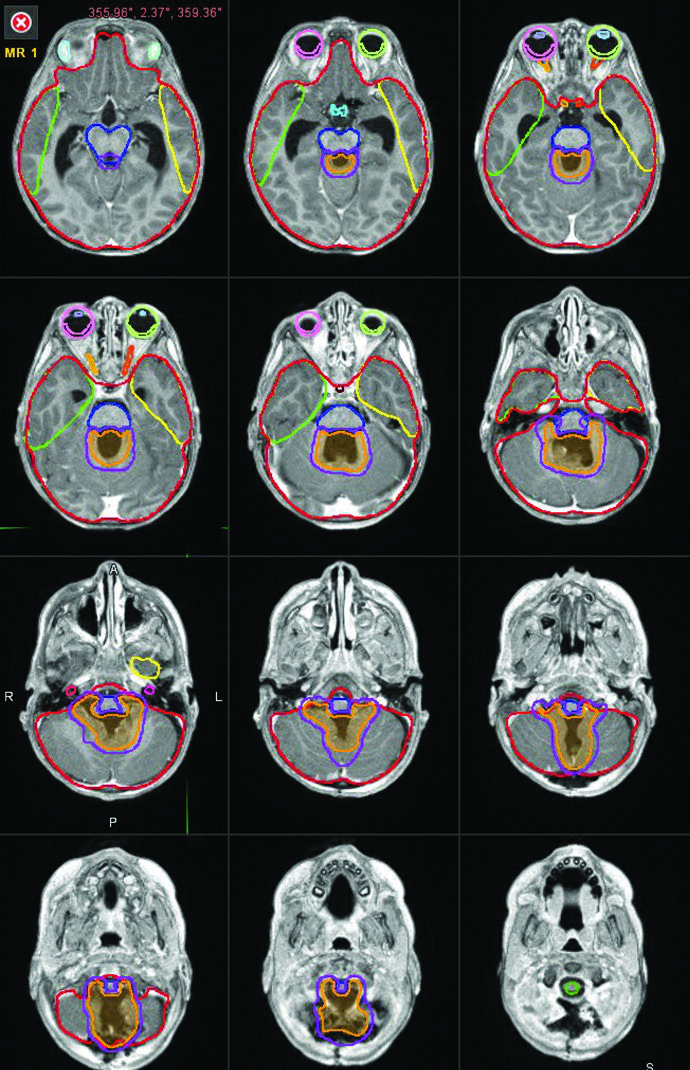

O delineamento de tumores cerebrais pediátricos exige estadiamento completo, imobilização reproduzível e margens anatomicamente disciplinadas. No capítulo dedicado a esse tema, o livro organiza a tomada de decisão em três cenários que realmente mudam dose, volume e lógica de boost: meduloblastoma, ependimoma e germinoma puro.

O texto é direto porque precisa ser. Em criança, alguns milímetros mudam o que entra no neuróeixo, no tronco encefálico e na medula cervical. Para uma visão ampla da série, confira o Target Volume Delineation and Field Setup – Complete Clinical Guide; aqui o foco fica no artigo detalhado de planejamento pediátrico.

Esse raciocínio começa antes do planejamento. O livro pede história clínica e exame físico completos, RM de encéfalo com contraste antes e depois da operação em cortes finos de 1 a 3 mm, RM de coluna com contraste e coleta de líquor para afastar disseminação. Sem esse pacote, a discussão de CSI, campo de boost e dose total fica incompleta.

A simulação por tomografia também é tratada como parte do tratamento, não como mera etapa administrativa. A recomendação é reproduzir a posição com Vac-Lok corporal inteiro ou alpha cradle, associado a máscara craniana com múltiplas marcações para triangulação e alinhamento longitudinal da coluna. Quando o software permite, o livro sugere cortes mais finos no crânio e cortes mais espessos ao longo da coluna para equilibrar detalhamento e carga de contorno. O exame deve cobrir todos os dispositivos de imobilização, o topo do crânio cranialmente e as gônadas caudalmente.

Na prática, a conversa com a anestesia antes de confeccionar a máscara evita retrabalho. O capítulo cita um ponto muito real: se a criança começa o tratamento intubada, mas depois deve seguir com máscara laríngea ou cânula nasal, vale considerar uma via aérea oral já na primeira máscara para manter o mento estável e não precisar ressimular por folga no molde. Esse mesmo cuidado vale para os órgãos de risco, que precisam ser contornados em todas as fatias do planejamento. Se a sua equipe ainda sofre com nomes inconsistentes entre PTV, tronco, quiasma e medula, ajuda revisar nosso artigo sobre padronização das estruturas em radioterapia (TG-263) antes de montar esses conjuntos.

O estadiamento segue uma linha parecida com a do meduloblastoma, embora a chance de disseminação ao diagnóstico seja menor, abaixo de 10% nos tumores intracranianos. O livro pede RM de encéfalo antes e depois da cirurgia, RM de coluna total e avaliação clínica detalhada. Salvo contraindicação médica, a citologia do líquor e a RM de coluna devem ser obtidas para excluir disseminação. Não é o achado mais comum, mas ignorar essa etapa pode rebaixar demais o volume.

A tomografia de simulação deve ser feita sem contraste, com 1 a 3 mm de espessura, incluindo todos os dispositivos de imobilização e toda a medula cervical. Como muitas dessas crianças precisam de anestesia diária, o capítulo reforça o planejamento conjunto com a anestesia para que a máscara acomode de forma reprodutível os dispositivos respiratórios necessários.

Na definição do GTV, os autores chamam atenção para dois pontos que costumam escapar quando se olha apenas a cavidade principal: os forames de Luschka e de Magendie. Conversar com o cirurgião ajuda justamente aí, porque alguns achados operatórios não aparecem com nitidez suficiente na RM. Esse é o tipo de detalhe que muda o contorno sem mudar o volume de forma grosseira.

Margens, conedown e proteção de estruturas críticas

O capítulo mostra uma redução gradual das margens ao longo da última década. No protocolo COG ACNS 0831, o tratamento foi planejado com CTV igual a GTV mais 0,5 cm até 54 Gy em 30 frações. Para conter toxicidade no tronco, a expansão para dentro do tronco encefálico foi limitada a 3 mm. Em crianças com mais de 18 meses, o mesmo protocolo usou conedown até 59,4 Gy excluindo totalmente tronco encefálico, quiasma óptico e medula cervical do boost final.

Na definição do alvo, o livro insiste num ponto muito prático: o volume pré-quimioterapia deve ser contornado logo no início do planejamento, antes mesmo do desenho ventricular, porque o boost frequentemente ultrapassa o contorno normal dos ventrículos. O alvo inclui doença pré-quimioterapia, doença residual e sistema ventricular. Para o boost, o CTV corresponde ao GTV pré-quimioterapia mais 1 a 1,5 cm. A inclusão da cisterna prepontina é opcional, mas deve ser considerada após terceira ventriculostomia e em tumores suprasselares volumosos.